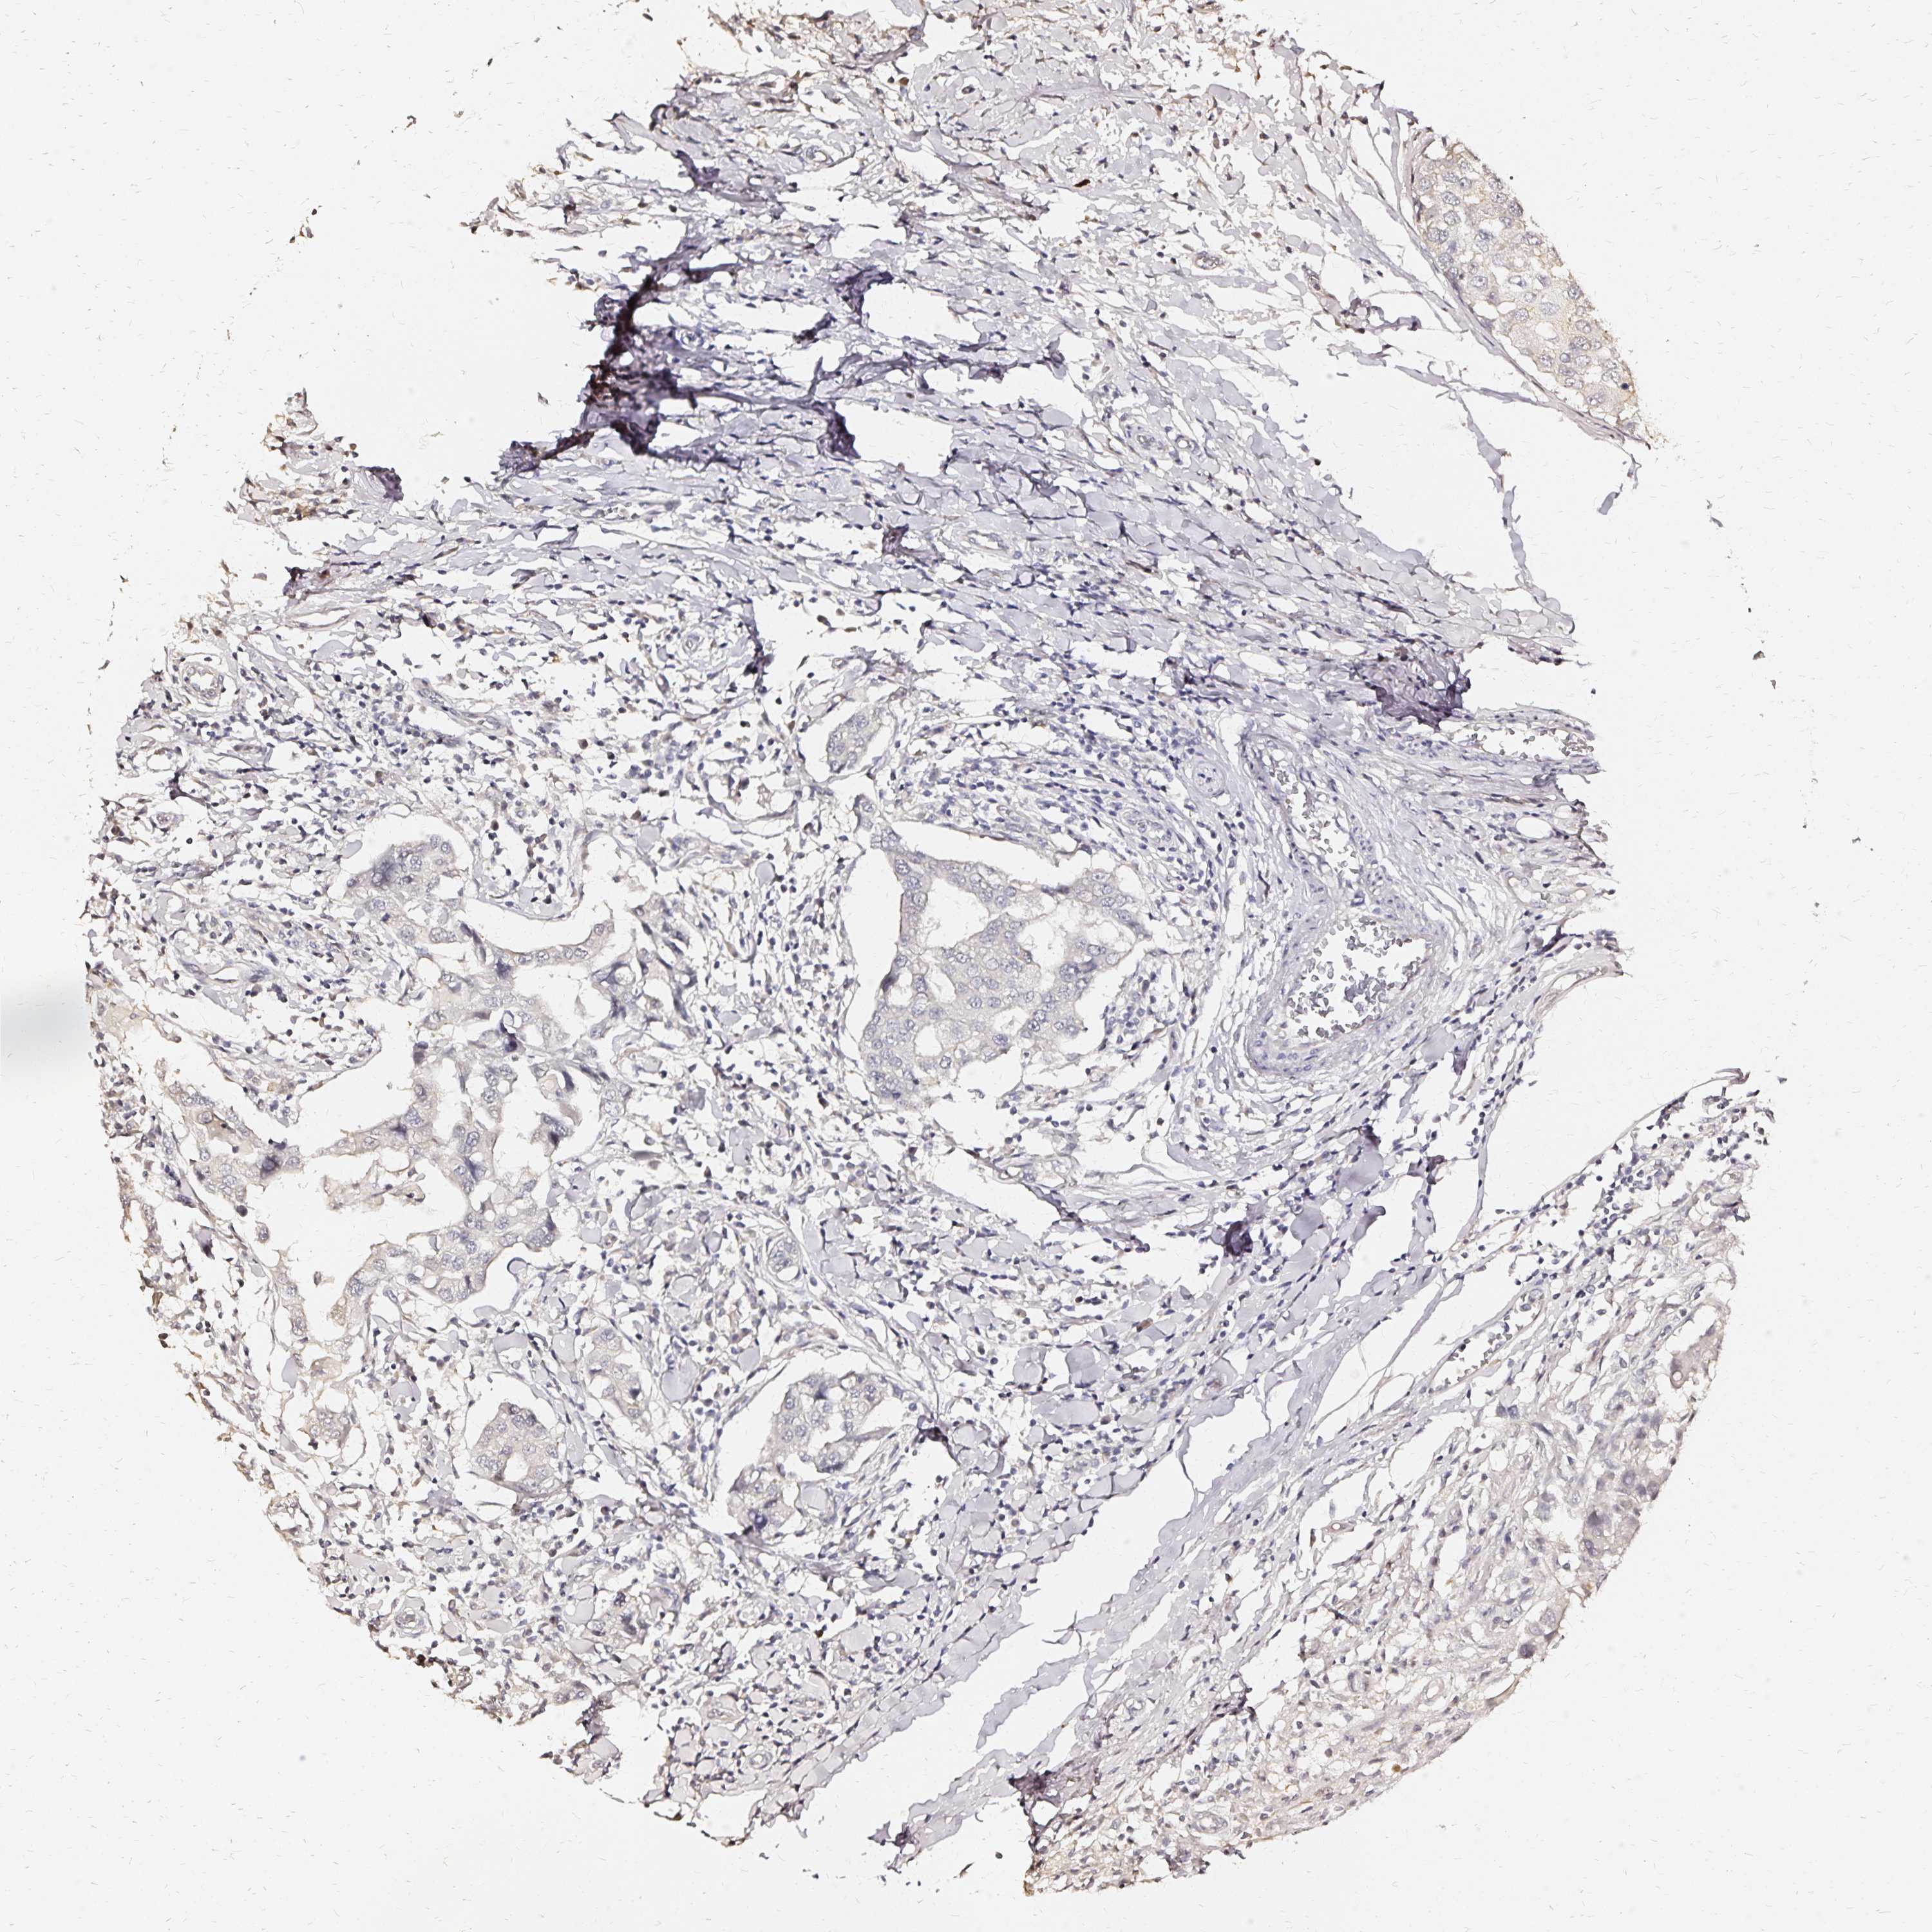

CANCER BREAST CANCER Show tissue menu

Breast cancer

Human cancer

Breast invasive carcinoma